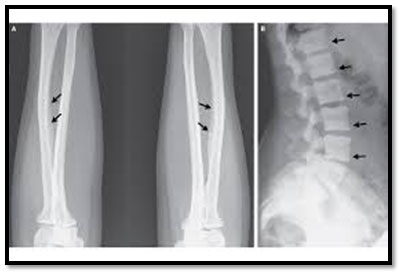

This disease causes crippling deformities of the spine and joints, especially in children whose skeletons are still forming.

Skeletal fluorosis is a serious condition, resulting from chronic ingestion of large amounts of fluoride over many years during periods of bone modeling (growth) and/or remodeling.

Obvious symptoms of fluorosis, which occurs in developing countries in particular, are brown-yellow stains on the teeth and bones and also long-term excessive exposure causes abdominal pain, excessive saliva, nausea, vomiting, seizures and muscle spasms.

In early symptoms of skeletal fluorosis the bones are generally weaker than normal with stiffness and pain in the joints as the early symptoms. However, in severe cases, the bone structure may change and ligaments may calcify, with resulting impairment of muscles and pain.